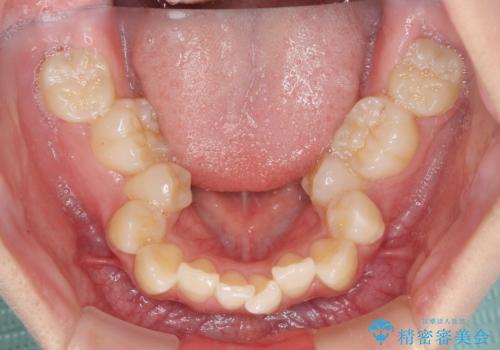

- 前歯の叢生と八重歯を気にして来院された患者様です。

叢生が強く、奥歯の咬合も左右差が大きかったため、上下左右4本を抜歯して、ワイヤー矯正を行うこととしました。